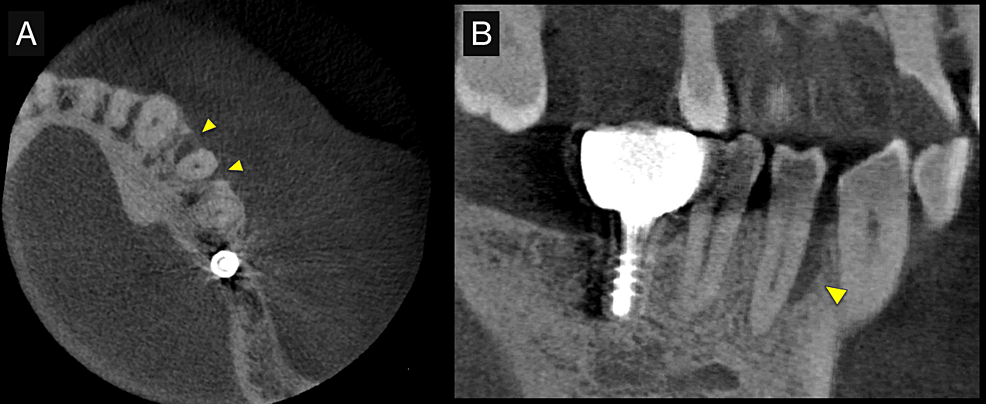

First, initial treatment including oral hygiene instruction was provided, followed by scaling and root planing. Teeth #16, #27, #37, and #46 were extracted, as they were considered too difficult to preserve. After reevaluation, a dental implant was provided for tooth #46. The patient was enrolled in supportive periodontal therapy after it was confirmed that the initial course of periodontal treatment had stabilized conditions. Subsequently, an acute periodontal abscess was observed in #44, however, requiring the start of anti-inflammatory treatment including periodontal pocket curettage under local anesthesia and oral antibiotics. Nevertheless, no improvement was found in the 6-mm buccal pocket of #44, so periodontal tissue regeneration therapy was planned. Before starting such treatment, in addition to intraoral radiography, cone-beam computed tomography (CBCT) was also performed using the 3DX Multi Image Micro CT (J MORITA Co., Ltd., Kyoto, Japan) (Figures 1, 2). The scan parameters were as follows: 90-kV tube voltage; 7-mA tube current; field of view, 60 mm x 60 mm; and slice thickness, 0.125 mm. The CBCT images revealed an intrabony, two-walled, defect around #44 that was slightly less radiolucent on the intraoral radiographic image. It was localized on the buccal side from the proximal to the distal aspect. A relatively large mandibular torus interior was also observed on the lingual side of #44 and #43.

Periodontal tissue regeneration therapy was selected as the surgical procedure to be used considering the maintenance of blood supply from the surrounding tissues as a priority. Prior to surgery, a 3D model was fabricated based on the preoperative CBCT images using a 3D printer.

The fabricated 3D model was then explained to the patient and a simulation was run to confirm the planned use of FGF-2 and the required amount is shown in Figure 3A. Photographs taken during the surgery are shown in Figure 3B–3D. The surgical procedure was performed under local anesthesia (2% lidocaine with 1:100,000 epinephrine). Just one incision was made on the buccal side of the gingival sulcus, and a simplified papilla preservation technique was employed to preserve a wide margin between the mucoperiosteal flaps at the interdental papilla incision [5]. The dissection to reveal the intrabony defect was kept to a minimum to maintain blood flow, with only the buccally attached gingiva being incised. A full-thickness mucoperiosteal flap was then developed. After completion of debridement, a relatively large intrabony defect was observed on the buccal side of #44 spanning the proximal to the distal aspects. Periodontal regenerative medicine (REGROTH®, Kaken Pharmaceutical Co., Ltd., Tokyo, Japan) was applied to the defect, and the flap was closed. It was also injected into the gap during suturing to avoid a decrease in volume due to leakage. After surgery, the patient was instructed to use a mouth rinse containing chlorhexidine (ConCool F®, Weltec Corp., Osaka, Japan) regularly for four weeks. No significant irregularities were observed postoperatively (no excessive swelling, and no suture breakage or infection) and the sutures were removed one week later. After that, the patient was instructed to brush with a soft-bristle toothbrush to prevent damage to the treated area. Brushing using the scrubbing method was started in the second week postoperatively. Meanwhile, the patient continued to receive constant professional care.